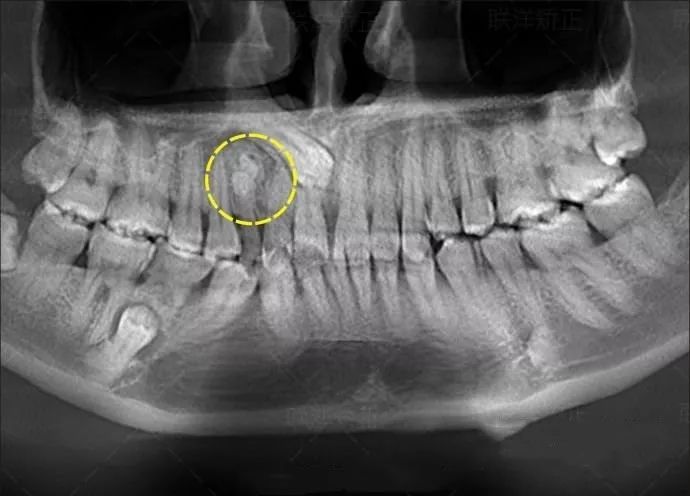

拍一次全口曲面断层

=22微西弗

=22张小牙片

=220根香蕉

等于坐飞机5.4小时

拍一次全口曲面断层=吃220根香蕉